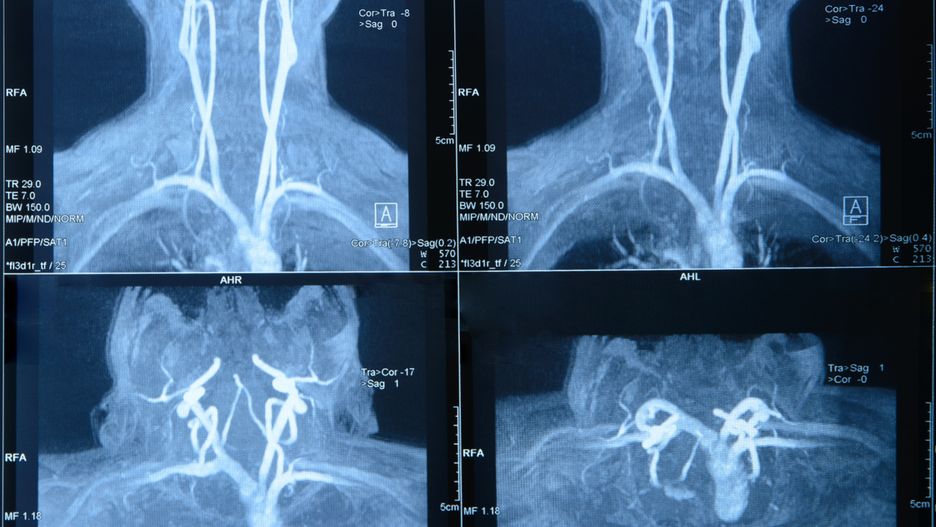

Rezonans magnetyczny szyi odbywa się w pracowni MRIRezonans magnetyczny szyi odbywa się w pracowni MRI

Źródło zdjęć: © Adobe Stock

Rezonans magnetyczny szyi (RM albo MRI, od ang. Magnetic Resonance Imaging) to badanie obrazowe wykorzystujące fale radiowe i silne pole magnetyczne. Uwidacznia zarówno struktury naczyniowe, jak i tkanki miękkie zlokalizowane pomiędzy szczytem płuc a podstawą czaszki. Sprawdza się w ocenie ślinianek, tarczycy, krtani, dolnej części gardła i przestrzeni przygardłowej oraz górnego odcinka przełyku. Struktury kostne znacznie lepiej widać podczas tomografii komputerowej.

Odmianę badania rezonansu magnetycznego szyi stanowi angio-rezonans magnetyczny, który wykorzystuje się do obrazowania zmian miażdżycowych w tętnicach szyjnych.